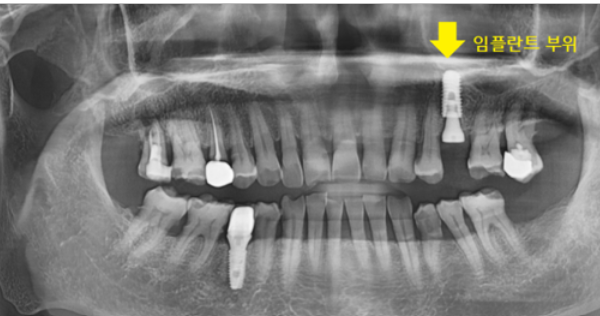

임플란트 진단을 위해 ct를 찍어보았는데

다른 치아도 뼈가 많이 녹은 것이 발견

환자분께 안 좋은 상황임을 안내해드렸습니다.

부러진 치아 바로 옆에였는데요.

하셨던 아말감 충전된 상태도 안좋았지만

잇몸 뼈가 많이 녹으셨어요.

치아 부러짐 부위만 우선적으로 임플란트 수술하였습니다.